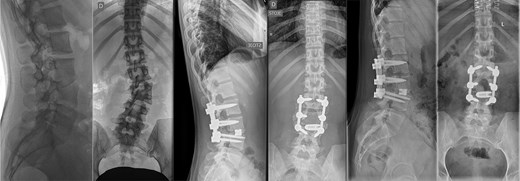

Last preoperative X-ray, lateral (A) and anteroposterior view (B). After 10 weeks of follow-up; lateral (C) and anteroposterior view (D). After 1 year of follow-up; lateral (E) and anteroposterior view (F).

The postoperative course was uneventful, with no evidence of neurological dysfunction. The patient commenced physiotherapy on the first postoperative day. At the initial follow-up, 10 weeks post-surgery, she was ambulating unassisted with reduced back and leg pain, without neurological impairment but with a persistent forward-leaning posture that remained correctable with verbal cues. At the final follow-up, one year after surgery, she reported resurgence of forward-leaning posture after longer walks, and referred to a tertiary rehabilitation institution. Imaging demonstrated L2–L5 fusion with no signs of instability or residual deformity (Fig. 1).

A 43-year-old female with a history of a previous isolated right-sided L3 foraminotomy at an external facility (this intervention temporarily alleviated her leg pain but exacerbated her back pain) was referred to our institution due to chronic back pain, right-sided leg pain without neurological dysfunction, and a forward-leaning posture, which was correctable with verbal cues. The back pain, in the absence of neurological deficits, began 13 years prior, at which time she was diagnosed with adult congenital scoliosis caused by L3 hemivertebrae (Figs 1 and 2). Imaging confirmed a L3 hemivertebra resulting in a 24° Cobb angle of congenital scoliosis (Fig. 1), without associated cord abnormalities on MRI.